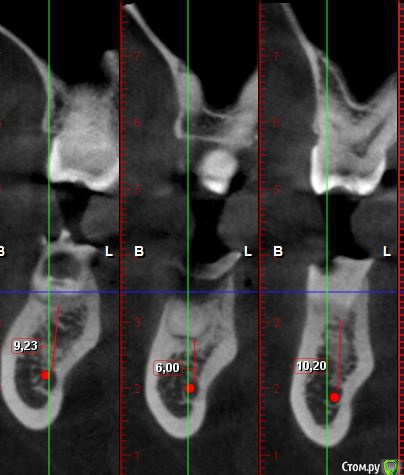

Irouil Опубликовано 22 ноября, 2017 Поделиться Опубликовано 22 ноября, 2017 Что за система имплантационная планируется? Нужен короткий имплантат с переключением платформ, если Анкилос то я бы графтил. В остальных случаях не стал бы, обошёлся бы сст и иф. Вы бы срезы на КТ по оси зуба показали и замеры в идеале от проекции края вестибулярной стенки на оси имплантата до пересечения оси с каналом. Думаю, выйдет миллиметров 11 Ссылка на комментарий

колесников Опубликовано 22 ноября, 2017 Поделиться Опубликовано 22 ноября, 2017 Не совсем корректные замеры для позиционирования импланта.Примите во внимание язычное поднутрение и вестибулярный край гребня. Думаю там рабочий размер 6мм. Если нет графта,я бы предложил ставить отсроченно. Имплант типа ТЛ,вестибулярно сст. Хотя мой выбор, при таком раскладе ,это одномоментно профайл с графтом и сст. 1 Ссылка на комментарий